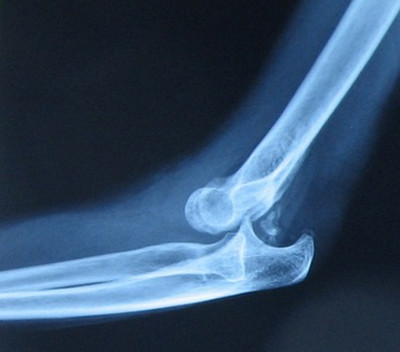

Боль в локтевом суставе, поддержка предплечья здоровой рукой. Область локтевого сустава деформирована, наблюдается припухлость и кровоизлияние. Предплечье находится в положении неполного фиксированного разгибания (120-140°) и слегка пронировано. Плечо кажется удлиненным, предплечье — укороченным. Ось предплечья смещена кнутри или кнаружи от оси плеча. Локтевой отросток выступает кзади; между разгибательной поверхностью нижнего отдела плеча и локтевым отростком видно дугообразное углубление. Головка лучевой кости выступает сзади и снаружи. Длина окружности на уровне локтевого сгиба и локтевого отростка на стороне вывиха увеличена. Верхушка локтевого отростка находится на 2-3 см выше мыщелков плеча. Активные и пассивные движения невозможны; при попытке движения определяется симптом пружинящего сопротивления.

Больному вводят 1 мл 1% раствора морфина. Вправление можно проводить под наркозом или местным обезболиванием. В сустав вводят 20 мл 2% или 30 мл 1% раствора новокаина. Больного укладывают на стол, плечо отводят до прямого угла. Хирург охватывает плечо над локтевым суставом, один палец на сместившемся локтевом отростке, другой — на головке лучевой кости. Помощник удерживает предплечье в нижней трети и кисть. Хирург и помощник плавно растягивают руку, сгибая ее в локтевом суставе. Хирург сдвигает локтевой отросток и головку лучевой кости. Обычно вывих вправляется легко, и больной может свободно двигать локтевым суставом. Рентгенологический контроль необходим до и после вправления.

После вправления локтевой сустав фиксируют гипсовой шиной под прямым углом, придавая предплечью положение супинации. Повязку накладывают на 5-10 дней в зависимости от повреждения связок и склонности к повторному вывихиванию. Со второго дня начинают лечебную гимнастику — движения в пальцах и плечевом суставе. После снятия гипса назначают движения в локтевом суставе, постепенно увеличивая силу и объем: сгибание, разгибание, пронацию и супинацию. Массаж и пассивные движения противопоказаны, так как в окружающих тканях могут развиваться оссифицирующие процессы, ограничивающие функцию локтевого сустава.